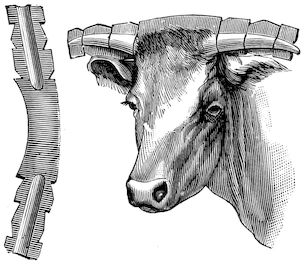

Fig. 9.—C, horn; P, modified skin forming the keratogenous membrane; O, horn core, exhibiting a double sinus.

(2.) The horn-secreting membrane is formed by the skin, which undergoes special development around the base of the horn and comes to resemble that of the coronary band, from which the hoof or claw is secreted. The band is about one-fifth of an inch in breadth. The papillæ of the dermis are specially developed at this point, and the epithelium which they secrete eventually forms the horn.

The internal surface of the growing horn is adherent to the horn core through the medium of another tissue formed by a specially differentiated periosteum which is continuous with the periosteum covering the frontal bone. It is not a true periosteum, but a vascular tissue formed of papillary layers analogous to those of the podophyllous tissue of the ox’s claw or horse’s hoof.

This keratogenous membrane receives a rich vascular supply from the arterial circle formed at the base of the horn core by a division of the external carotid, the blood conveyed by which is freely distributed to the enlarged papillæ. The great vascularity of these parts 23explains why lesions of the horns are often followed by such profuse bleeding.

(3.) The horn secreted by the papillæ of the horn band (which is analogous to that of the coronary band of the horse) forms a cone varying in its curve in various breeds. Its base is hollow, and contains little depressions holding the papillæ from which the horn is secreted. From its base up to the end of the horn core the walls progressively increase in thickness. From this point it is solid; in a fully-grown horn the bone does not extend more than one-half or two-thirds of the entire length.

In the adult, the development of the horns varies with different breeds and is affected by sex. In the bull the horns are short, but in the cow and ox long. Short and fine in animals of improved breed like the Durham, they are long and thick in breeds of working oxen.

Anatomy of the horns. The horns form organs of defence, and project on either side of the frontal bone at the poll. Each consists firstly of a bony basis generally known as the horn core; secondly, of a horn-secreting membrane; thirdly, of a horny sheath, the horn properly so called.

22(1.) The horn core projecting from the frontal bone does not develop until after birth. About the third month a little prominence appears under the skin, which, as it develops, assumes a conical shape, and may be seen to be covered with a horny substance. In proportion as the horn core grows, there develops within it a cavity which may either be of a simple character or divided by a longitudinal partition. This communicates with the frontal sinus, a fact which explains the collection of pus in the sinuses as a result of injuries to the horns. The sinus of the horn core does not exist in young animals, and is not completely developed before the third or fourth year of life.